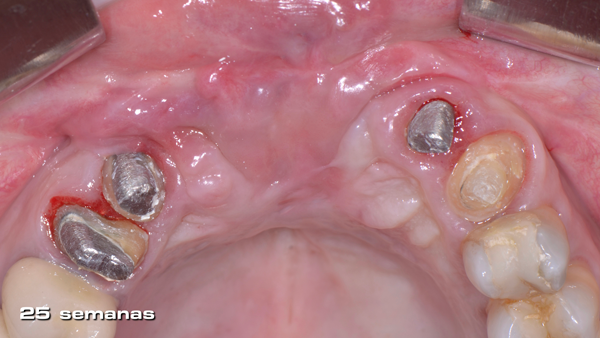

Uma vez que a membrana foi completamente fixada, o retalho foi mobilizado para permitir o fechamento primário livre de tensão. O retalho foi suturado em duas camadas: primeiro, as suturas horizontais em colchoeiro e, depois, as suturas simples para fechar as bordas do retalho (Figura 10). As suturas simples foram removidas 14 dias após a cirurgia e as suturas em colchoeiro horizontais foram removidas três semanas mais tarde. A membrana foi então removida após 25 semanas de cicatrização usando um retalho crestal de espessura total (Figuras 11 a 14).

Combinando o aumento vertical do rebordo com a incisão “invertida” observa-se maior previsibilidade nas regenerações ósseas guiadas. No entanto, normalmente ocorre a translocação coronal severa da linha mucogengival e a perda do vestíbulo e mucosa ceratinizada, que precisam ser resolvidos com um novo procedimento cirúrgico de aprofundamento de vestíbulo e ganho de mucosa ceratinizada. Portanto, no próximo caso de regeneração, por que não tentar o retalho invertido? Até a próxima.